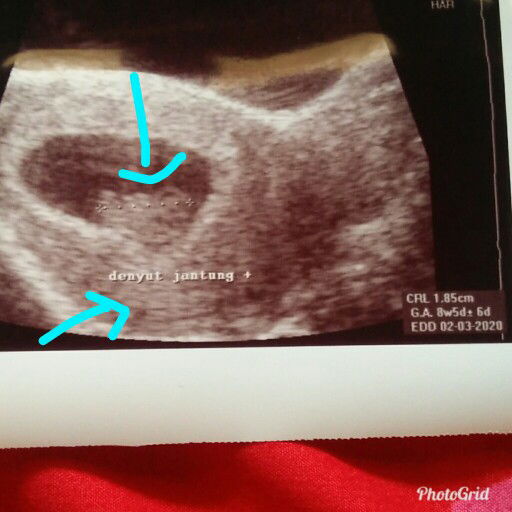

Yg di kasih tanda panah itu kata dokter djj itu usg pas 8w tapi barusan kunjungan ke bidan 15w tapi djj nya blm kedengran katanya tapi perkembangan perutnya sesuai dgn usia kandungan nya katanya ..wajarkah itu ?

detak jantung

Bun kira" harus worry ga ya kalo usia kehamilan 15minggu tapi detak jantung dede bayinya belum kedengeran ?